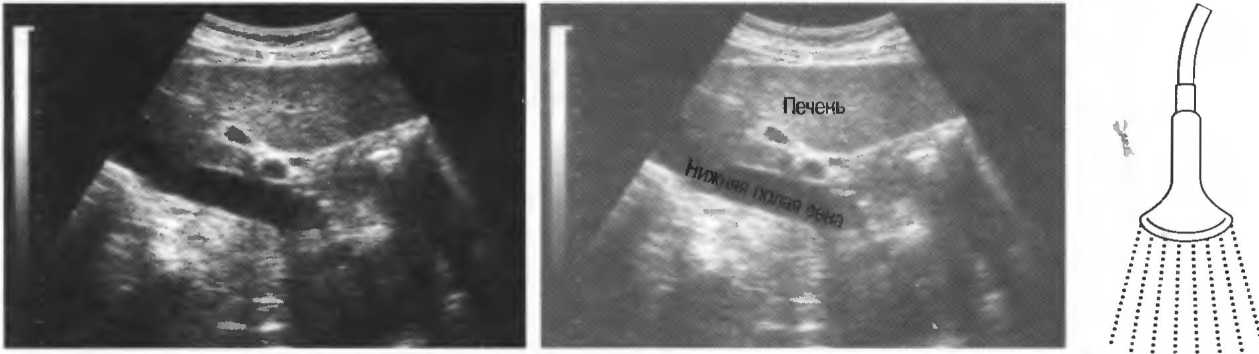

4. У здоровых обследуемых паренхима печени должна быть немного более эхогенна. чем кора рядом расположенной почки (рис. 26).

Рис.26. Продольный срез через печень и правую почку: нормальная паренхима печени более эхогенна, чем паренхима нормальной почки. Это еще один способ проверки качества изображения.